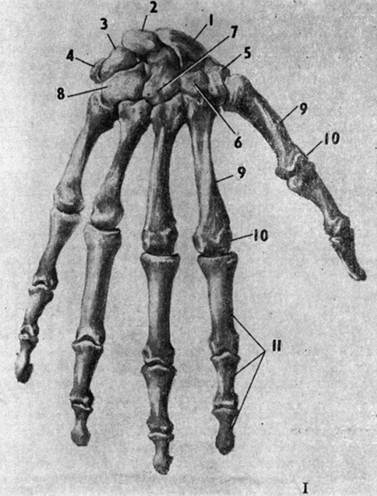

Анатомия кисти руки и строение костей